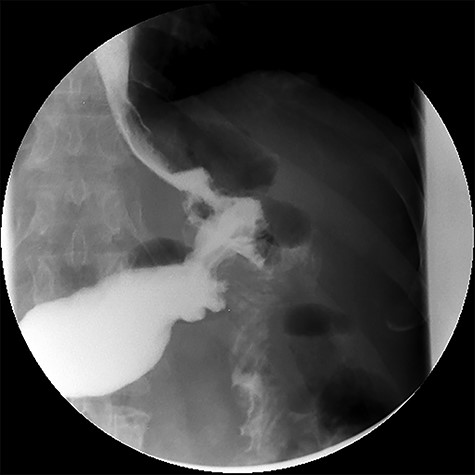

Three months after endoscopic treatment, the patient started complaining of epigastric pain again, without other gastrointestinal symptoms or weight regain. An upper gastrointestinal (GI) contrast swallow study showed recurrence of the GGF and GJA stenosis (see Fig. 4).

Upper gastrointestinal contrast swallow study image where it is possible to see a gastro-gastric fistula with opacification of the excluded stomach.